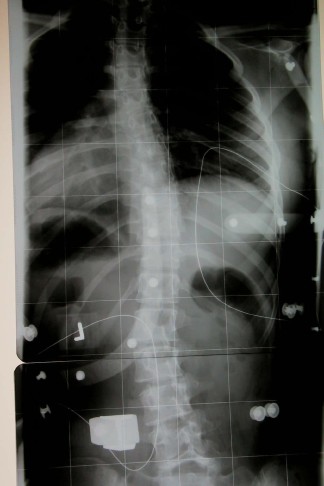

- Die 50° Cobb-Skoliose einer 16-Jährigen vor der Korsett-Therapie

- 50° Cobb.o.K.jpg (29.18 KiB) 6939 mal betrachtet

- So sieht eine 50° Skoliose mit 70% Primärkorrektur nach nur 2 Wochen im Rahmouni-Korsett aus!

- Im Korsett.jpg (28.78 KiB) 6939 mal betrachtet